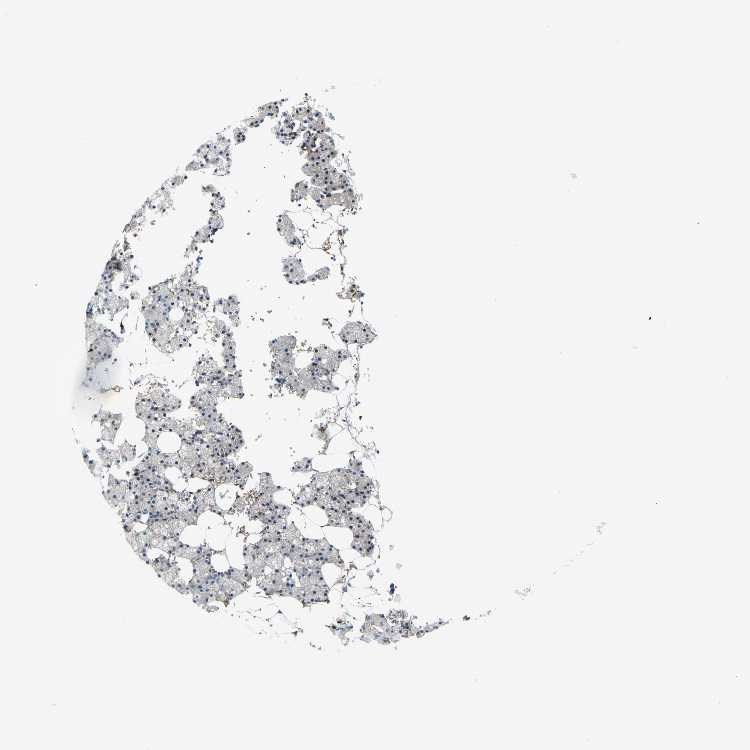

SALIVARY GLAND - Antibody stainingi

Antibody staining in the annotated cell types in the current human tissue is reported as not detected, low, medium, or high, based on conventional immunohistochemistry profiling in selected tissues. This score is based on the combination of the staining intensity and fraction of stained cells.

Each image is clickable and will lead to virtual microscopy that enables deeper exploration of all samples and also displays staining intensity scores, fraction scores and subcellular localization as well as patient and tissue information for each sample.

Antibody CAB011618Antibody CAB070164

Glandular cells MediumMedium